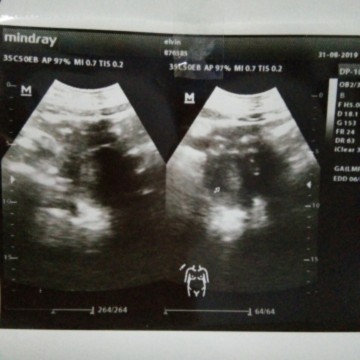

Bun kalo 4w kyk gni normal ga sih bun